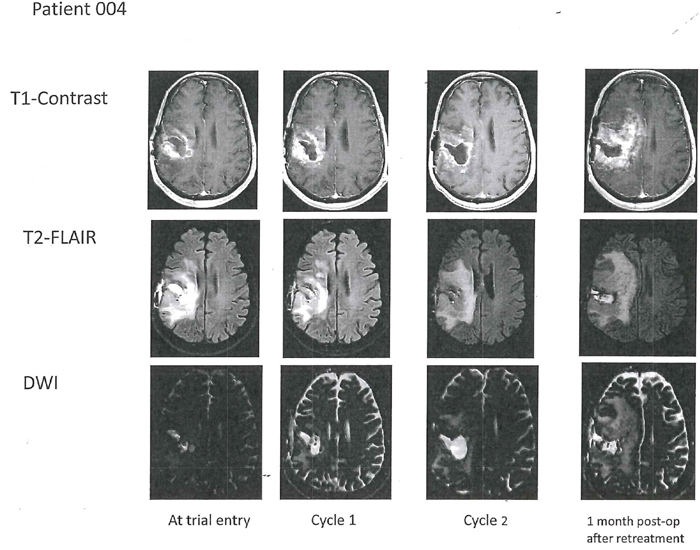

Patient 4 was a 57 year-old man whose original tumor was an IDH1/2 wild type anaplastic astrocytoma with unmethylated MGMT promoter and PTEN deletion (Table 1). At trial entry, re-operation demonstrated that the tumor had become a glioblastoma. There were some residual areas of treatment effect. After cycle 1 on AXL1717, 300 mg bid, there was evolution of “salt and pepper” peri-tumoral contrast-enhancement on MRI that was worse after the second cycle necessitating an increase in his dexamethasone dose. (See Patient 4 serial MRI examinations in Figure 3). Re-operation/tumor re-resection histopathology demonstrated abundant areas of tumor necrosis and small areas of viable tumor. Because of this encouraging result he was treated with a third cycle of AXL1717, 300 mg bid, but was then taken off the study when he developed further clinical decline. He died 11 months later with MRI suggestive of progressive disease. An autopsy was not performed.

Figure 3: Axial T1-weighted contrast-enhanced images (top row) in Patient 4 with right temporal glioblastoma at trial entry with corresponding T2-FLAIR (middle row) and corresponding DWI with apparent diffusion coefficient (ADC) sequences (bottom row). After two cycles with AXL1717 there was enlargement of the tumor cavity. Surgical resection histopathology showed abundant necrosis with small islands of viable tumor. Progressive disease on imaging (and clinically) after an additional treatment cycle (post-operative; last column) and the patient was removed from the trial. T2 FLAIR shows increased edema post-operatively one month after treatment.